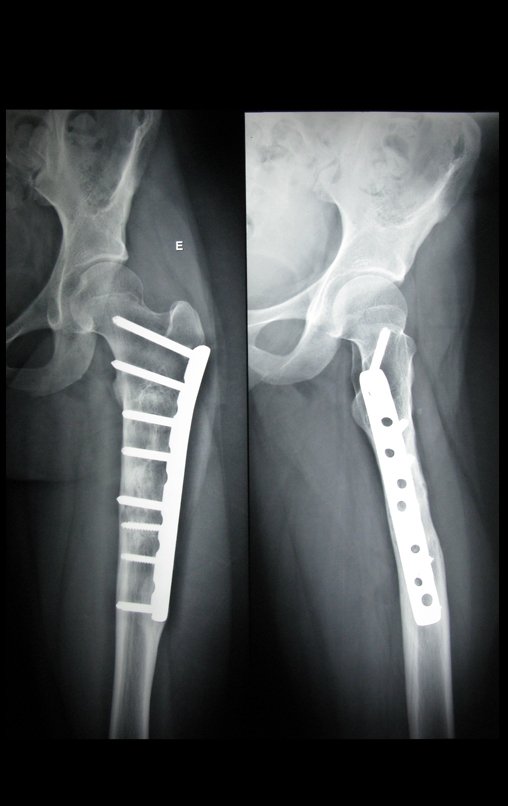

Quiste óseo simple del fémur

Quiste óseo femoral simple. Paciente femenina de 12 años, al evaluar su dentición con una radiografía panorámica, fue remitida a fisiatra debido a la variación anatómica de la columna.

El Fisiatra solicitó un escanógrafo de miembros inferiores y recomendó Pilates, sin diagnosticar la lesión en el fémur izquierdo. Posteriormente acudió a un pediatra que le diagnosticó la lesión.